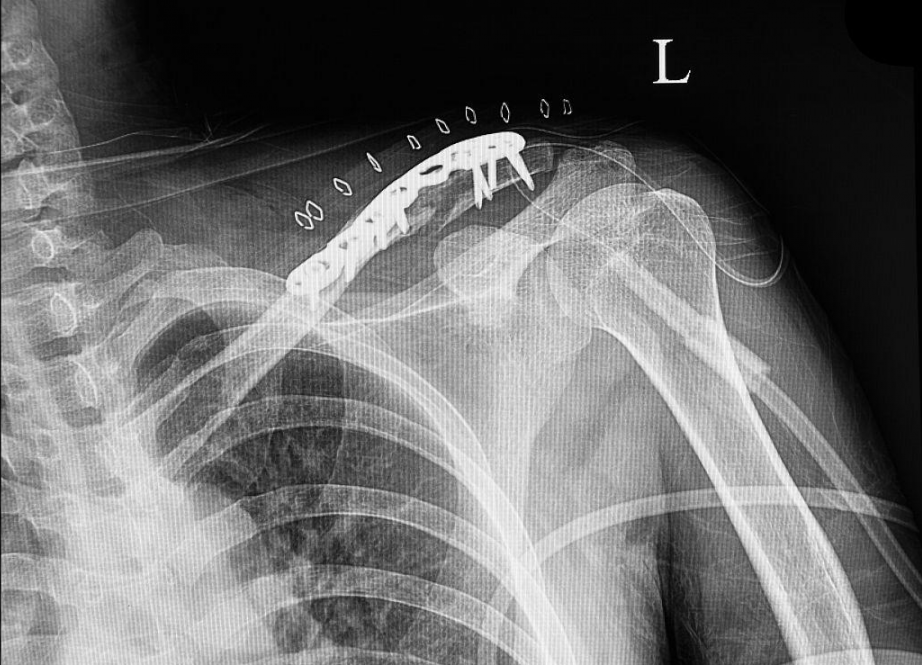

切开复位的治疗一般与内固定同时使用,治疗后,患者不需要涂抹石膏进行外固定。